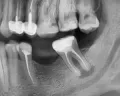

Отвалилась старая пломба, которую ставили девять лет назад. Пришел к стоматологу, она осмотрев сказала, что надо зачистить и заново запломбировать. Начав процедуру чистки, она попробовала пошатать зуб, потом сказала, что нужно сделать снимок. Снимок сделали, ее вердикт — надо удалять зуб, поскольку пошло воспаление вокруг корней, если его лечить со штифтами или еще как, через некоторое время он снова даст о себе знать и все равно придется удалить.

Есть ли смысл обратиться к другому специалисту? Или поверить и удалить?

Смысл конечно всегда есть, но если диагноз доктора подтвердится (воспаление на корнях), то скорее всего зуб придётся удалить.